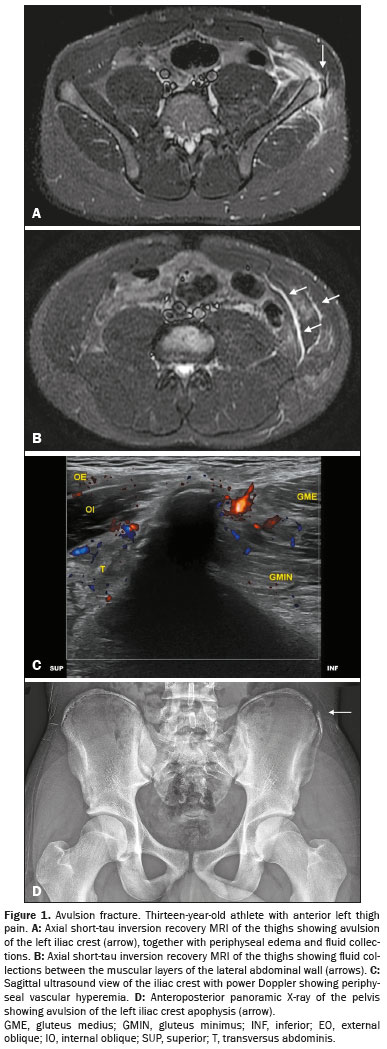

The study sample comprised 33 male athletes who underwent MRI scans. The mean age of the participants was 13.1 ± 1.7 years. Suspected injuries to the right lower limb were reported in 17 athletes (51.5%). The most commonly affected apophyses, in descending order, were the anterior inferior iliac spine, in 14 cases (42.4%), the ischial tuberosity, in 12 (36.4%), the iliac crest, in three (9.1%), the anterior superior iliac spine, in three (9.1%), and the lesser trochanter of the femur, in one (3.0%). Figures 1, 2, and 3 show exemplary images of the injuries.

The MRI scans revealed avulsion injuries in 21 athletes (63.6%) and apophysitis in 11 (33.3%). Only one athlete (3.0%) had normal MRI findings. The MRI findings for the cases of avulsion fracture included apophyseal displacement in all 21 cases (100%), periphyseal edema in 20 cases (95.2%) (Figures 1A and 3A), bone marrow edema in six cases (28.6%), and intermuscular fluid collections in 14 cases (66.7%) (Figure 1B). In cases of apophysitis, periphyseal edema was observed in five cases (45.5%). As illustrated in Figure 2, bone marrow edema was noted in all 11 cases of apophysitis (100%). Intermuscular fluid collections were identified in only two (9.5%) of the 21 athletes with avulsion fractures.

Power Doppler examinations were conducted in 31 athletes, showing vascular hyperemia, as shown in Figure 1C, in 10 cases (32.3%).

A total of 25 athletes underwent X-ray, which identifying avulsion fracture, as depicted in Figures 1D, 3B, and 3C, in 11 cases (44.0%). The median displacement observed on X-ray was 4.7 mm (range, 2.5–7.5 mm).